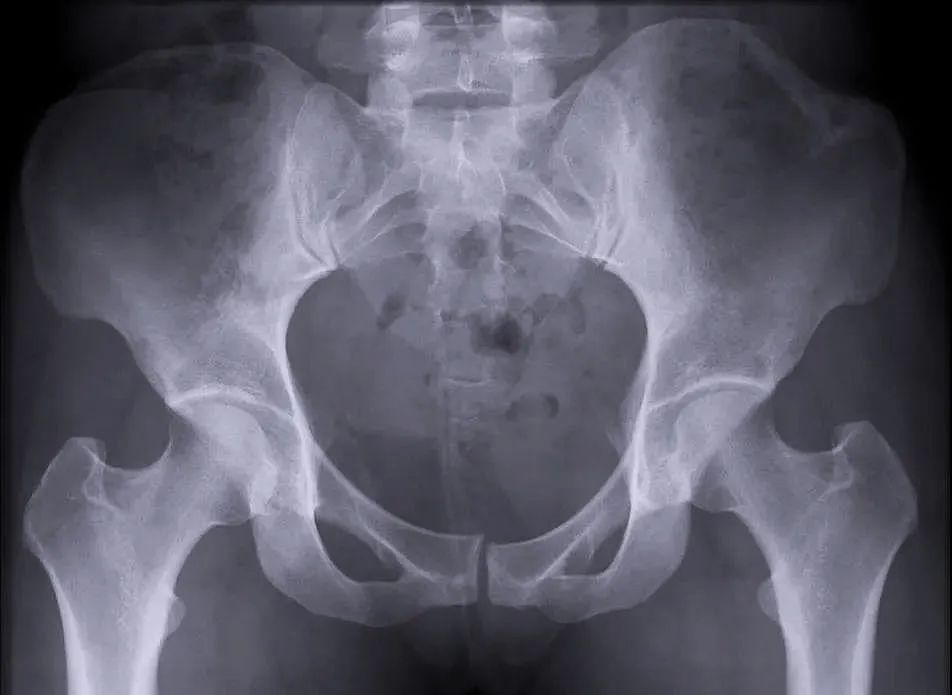

【医疗科普】:稳定性骨折影像

稳定性骨折

二、稳定性骨折&不稳定性骨折

另外,我们根据骨盆骨折是否稳定可以分为稳定性的骨折和不稳定性的骨折。如果是不稳定性的骨折医生可能会建议病人进行手术治疗,把不稳定性的骨折变成稳定性的骨折。